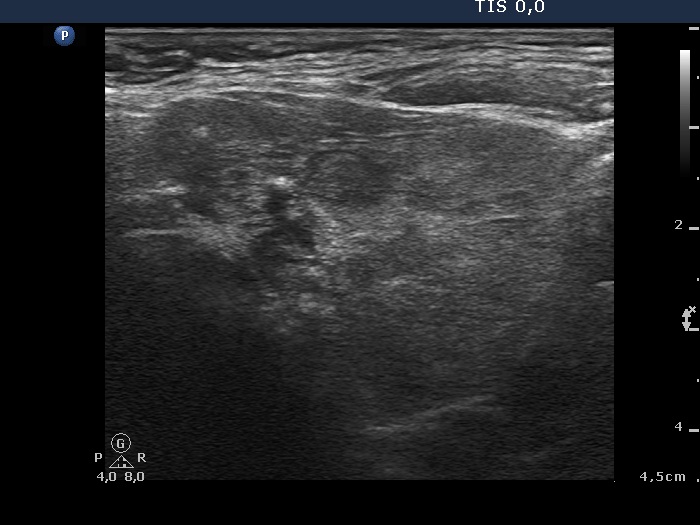

Ultrasonography. The thyroid was minimally hypoechogenic and had multiple discrete lesions which were mostly echonormal. The thyroid had a pseudonodular pattern. There were several hypoechogenic discrete areas.

Cytology from a hypoechogenic lesion in the lower pole of the left lobe resulted in benign colloid goiter.

Histopathology disclosed diffuse goiter and benign hyperplastic nodules in both lobes.